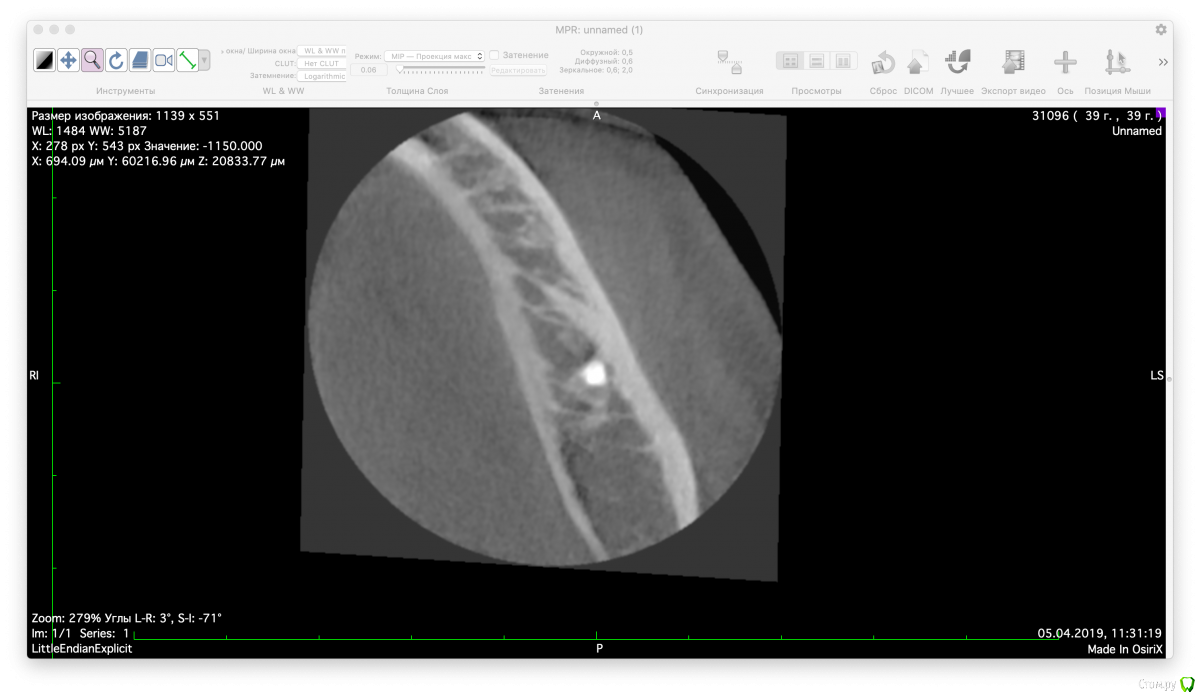

Valerkaa Опубликовано 15 мая, 2019 Поделиться Опубликовано 15 мая, 2019 Добрый день, коллеги. Только начинаю свою работу в сфере имплантации. Планируется имплантация в области отсутствующего 3.6, меня смущает наличие ранее выведенного пломбировочного материала. Понимаю, что при формировании ложа под имплантат материал фрезой не удалится, смущает просто само наличие материала вблизи будущего имплантата. Доставать или оставить все как есть? Заранее спасибо. Ссылка на комментарий

red_butler Опубликовано 15 мая, 2019 Поделиться Опубликовано 15 мая, 2019 не трогать материал 2 Ссылка на комментарий

kramer Опубликовано 15 мая, 2019 Поделиться Опубликовано 15 мая, 2019 Оставьте, не будет ничего 2 Ссылка на комментарий